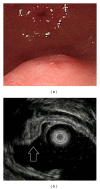

Gastric ectopic pancreas is an uncommon developmental anomaly and its histological diagnosis is usually difficult by using a conventional biopsy forceps. In the literature, most cases of gastric ectopic pancreas were usually diagnosed by gross pattern during endoscopic examination or features of endoscopic ultrasound. In contrast, this disease was seldom diagnosed by histology in clinical practice. Although the typical endoscopic ultrasonographic features of ectopic pancreas include heterogeneous echogenicity, indistinct borders, and a location within 2 or more layers, it can also exhibit hypoechoic homogeneous echogenicity and a distinct border within the fourth sonographic layer (muscularis propria) similar to the endoscopic ultrasonographic features of gastrointestinal stromal tumors. In our study, we found that 53% of gastric ectopic pancreas originated within the fourth sonographic layer, demonstrating hypoechoic, homogeneous echogenicity, and distinct borders. Therefore, recognizing endoscopic ultrasonographic features, combining with deep biopsy, endoscopic ultrasound-guided fine needle aspiration/core needle biopsy can prevent conducting unnecessary resection. Surgical resection is the mainstay treatment for symptomatic gastric ectopic pancreas, but endoscopic resection using endoscopic mucosal resection or endoscopic submucosal dissection technique provides an alternative method of removing superficial-type and deep-type gastric ectopic pancreas.